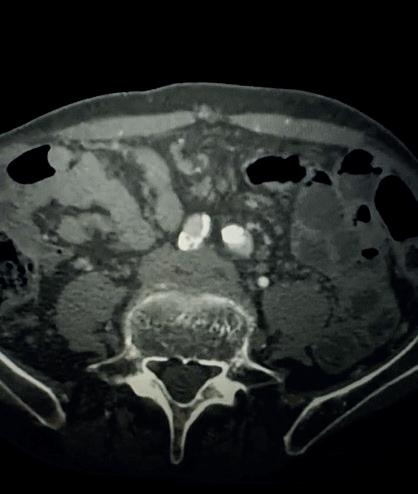

Case 1: The Shockwave L6 device in the setting of FEVAR and complex iliac stenosis

An 82-year-old man with a history of coronary artery disease (CAD), hypertension, hyperlipidemia, and peripheral arterial disease (PAD) presents with rest pain as well as

a large pararenal abdominal aortic aneurysm (AAA). His computed tomography angiography (CTA) revealed very dense and highly diseased iliac vessels with calcium deposition along most of the bilateral common iliac distribution.

The minimum luminal diameter (MLD) of the common iliac arteries measured roughly 4.5mm; however, the

“My experience with this system has taught me that appropriate balloon sizing is the single-most important predictor of a successful outcome”

healthy reference vessel diameter (RVD) was 9.5mm. He would require a fenestrated repair of the AAA along with complex iliac stenosis treatment, and extensive bilateral common femoral endarterectomies.

Further, we were concerned we would not be able to advance the 19F fenestrated graft. The endograft was prepared, and then both femoral arteries were exposed. We attempted delivery of the endograft via the right common iliac access. This failed. We then attempted delivery on the contralateral side. Despite multiple attempts, we made little progress. A 10x30mm Shockwave L 6 catheter was selected, and a total of 150 pulses were delivered to each iliac artery at just 4atm. This not only allowed for the delivery of our FEVAR graft but also the full unrestricted expansion of the endograft limbs in the common iliac arteries.

At the completion of the AAA, we took extra time to perform endarterectomies of the deep femoral arteries. His completion CT scan revealed a good seal of the AAA, patency of the renal fenestrations and unrestricted flow to the bilateral femoral arteries.

Figure 1. Pre-procdural CTA